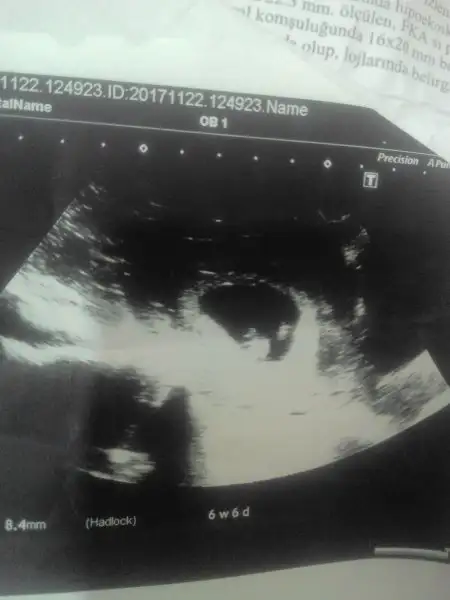

6. Haftaya ait usg resmi olduğundan emin misin?

evet canim bak atiyim tekrar 0

15150985798911465829701.webp